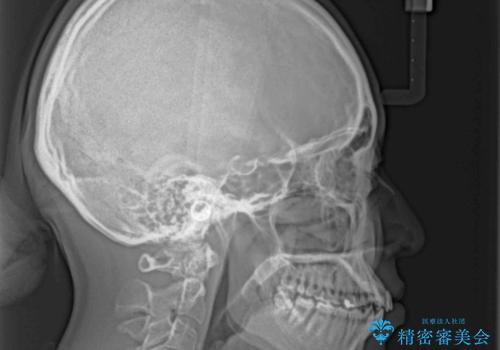

口元の突出感が認められ、更には左右で異なる咬合状態であったため、下顎右側は第二小臼歯を、左側は第一小臼歯を抜去することでバランスを取るような治療計画としました。